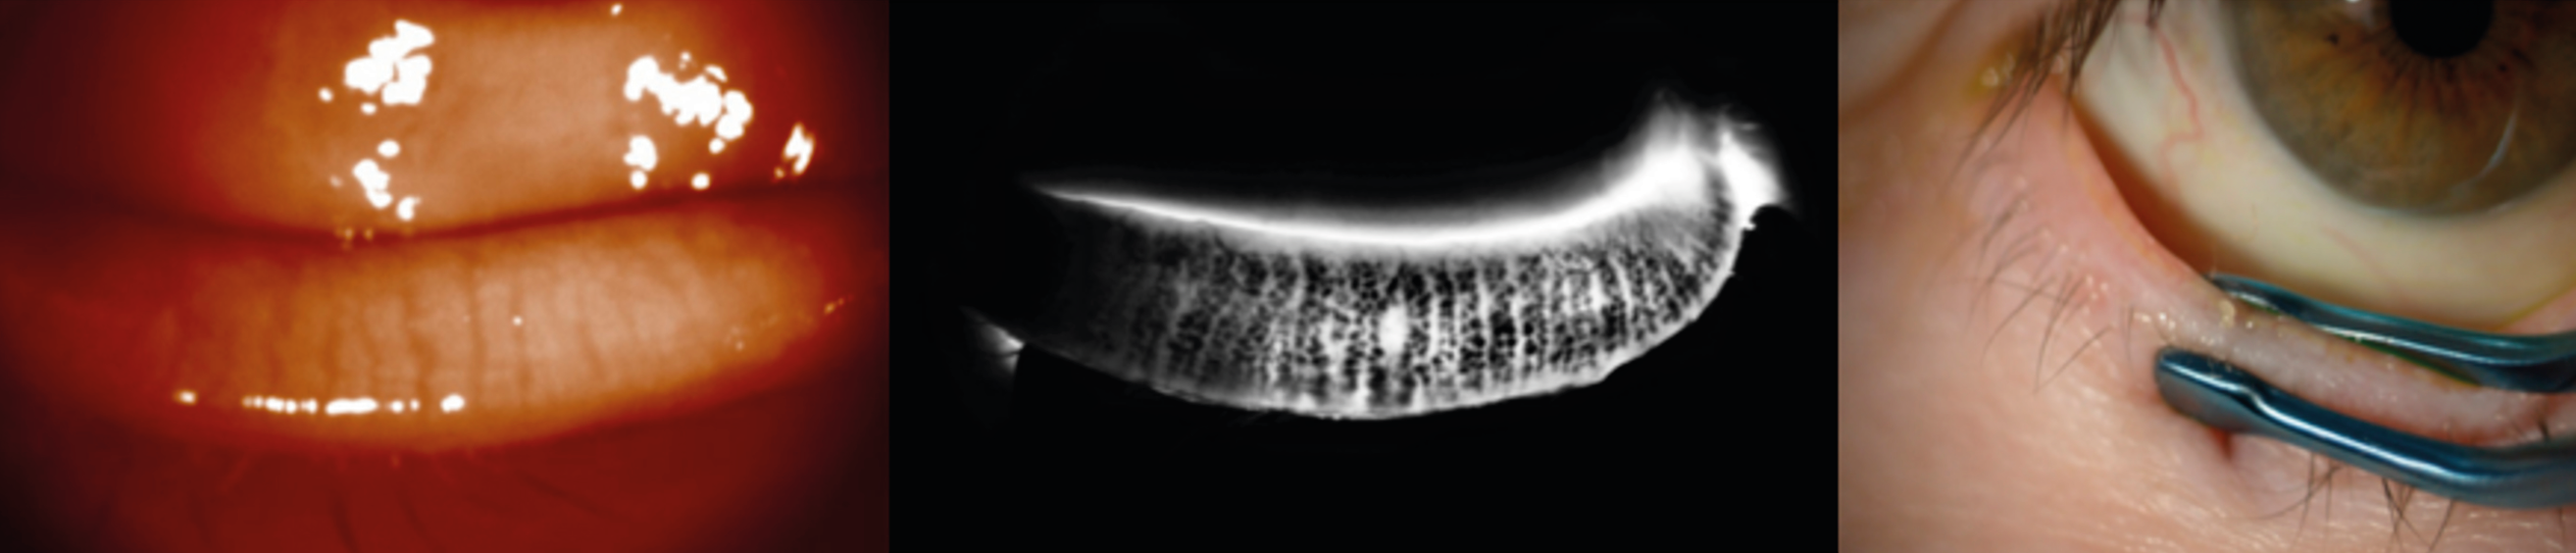

Figure 2. Examen à la lampe à fente avec la LRPG Menicon Rose K2 PG. À gauche : Examen lumière blanche : LRPG en position supérieure, corectopie et atrophie irienne en rapport avec le syndrome ICE. À droite : Examen à la fluorescéine après adaptation ; la lentille est prescrite à l’essai.

Figure 3. Examen à la lampe à fente de l’adaptation en piggy back avec LRPG Menicon Rose K2 PG et LSH Alcon Dailies Total One. À gauche : Examen à la fluorescéine satisfaisant, présence de bulles de pose ; il conviendra de revoir la manipulation pour les éviter. À gauche : Examen en lumière blanche, LRPG décentrée vers le haut.